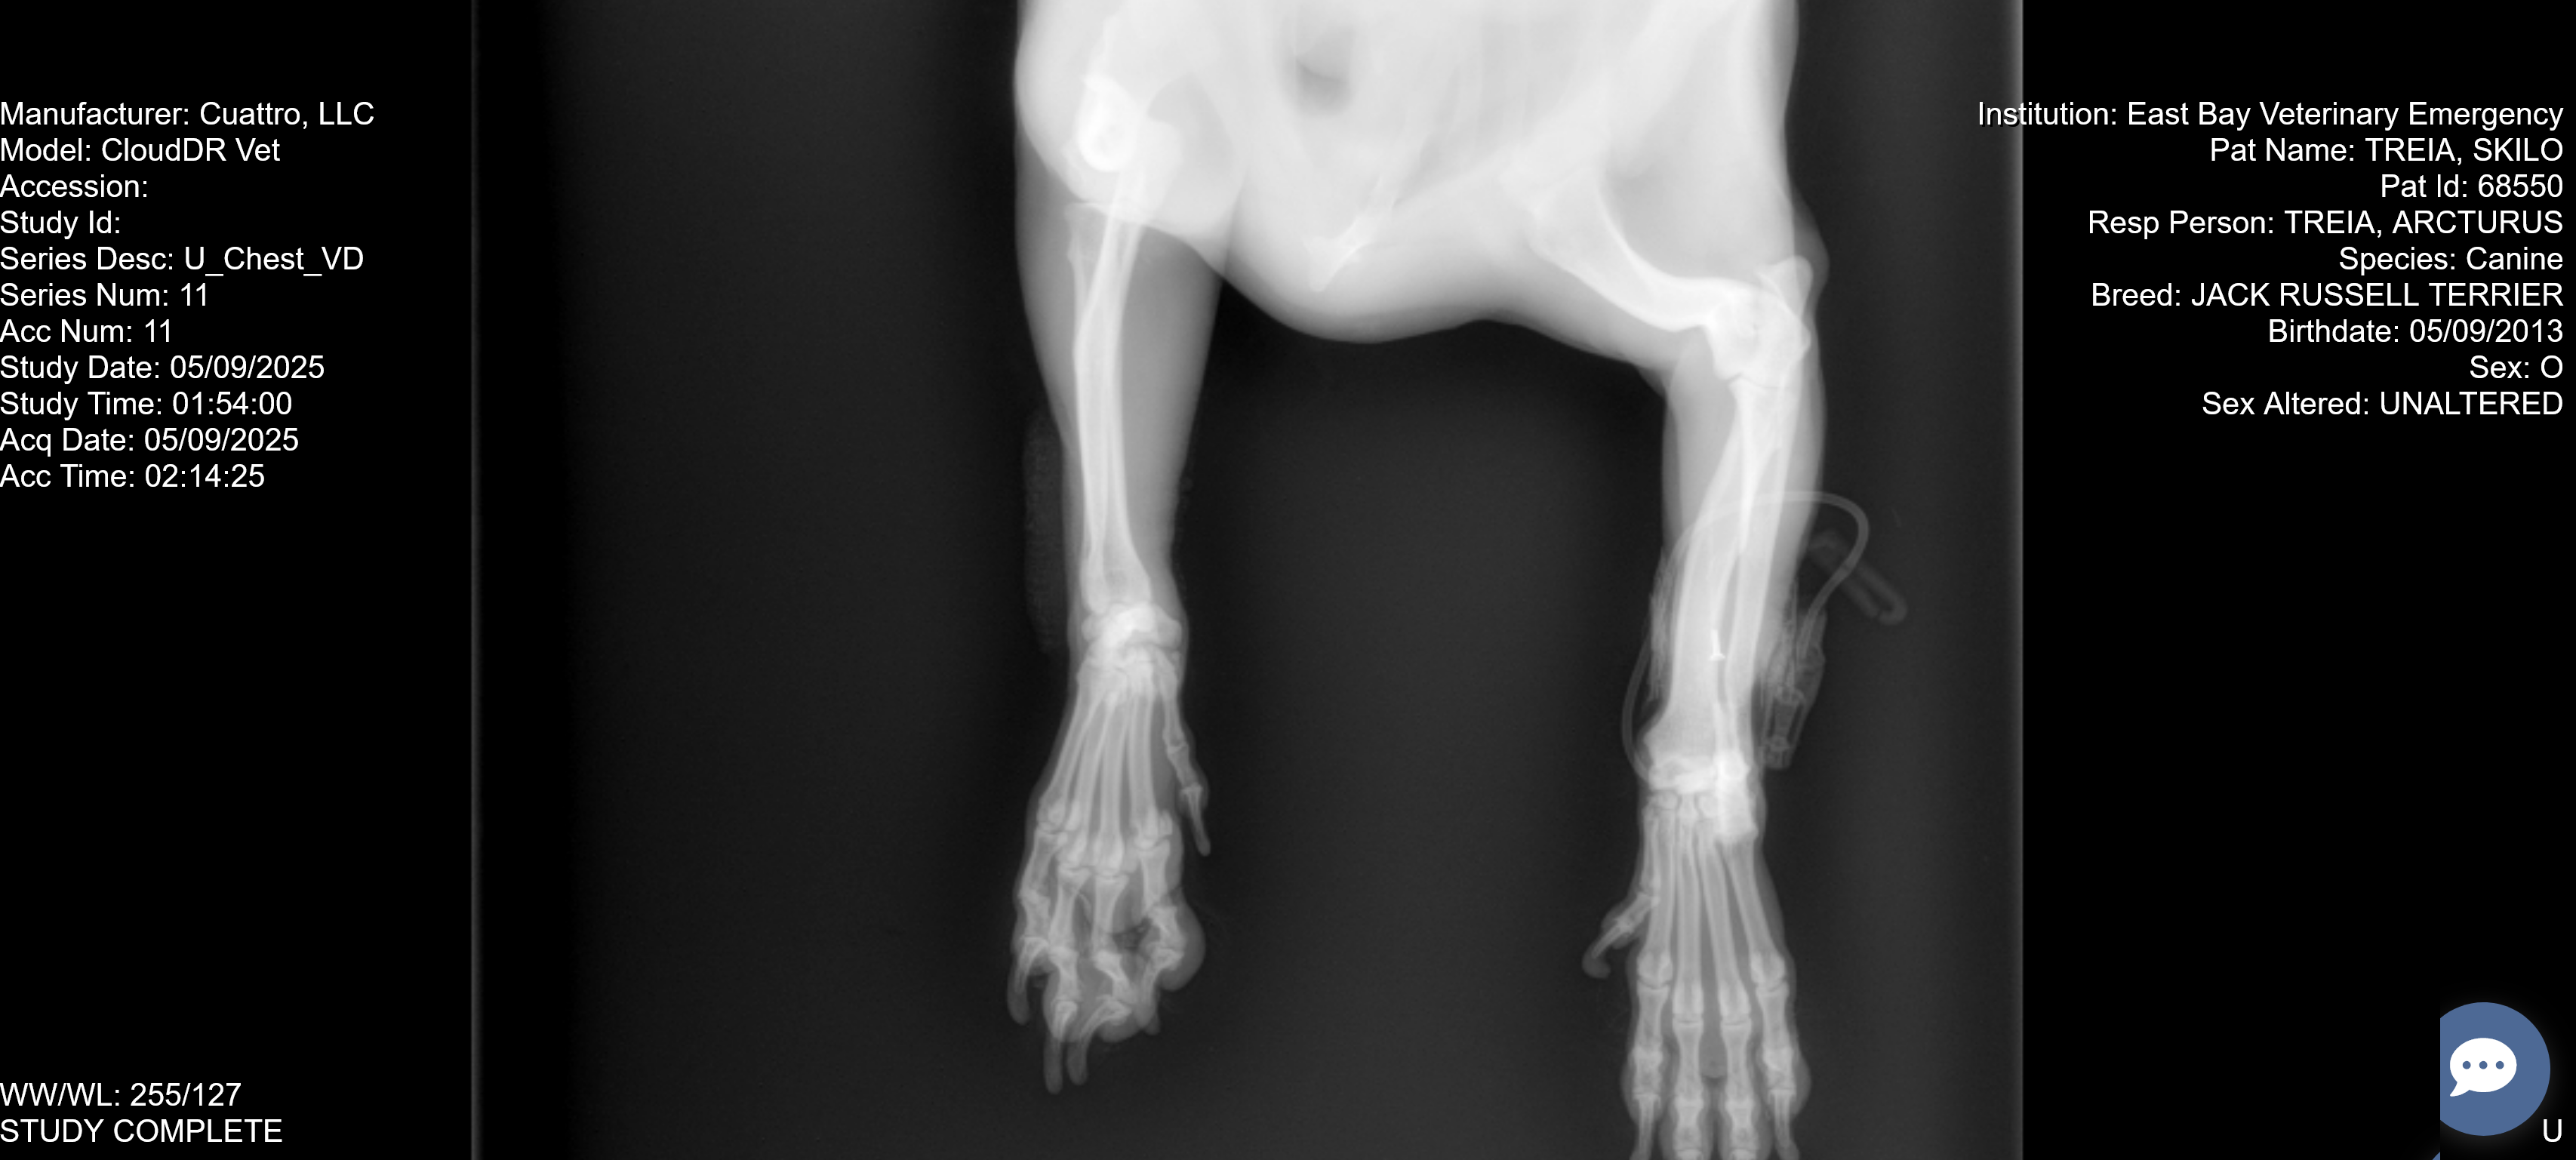

his right front humerus is broken.

Due to the location and severity of his injury,

he needs surgery to heal.